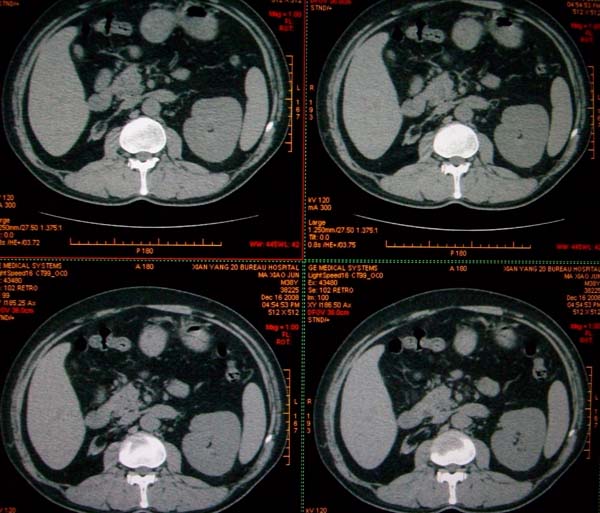

标题: CT17174:M38Y,体检超声提示右肾发育不良,病人无明显不适 [打印本页]

标题: CT17174:M38Y,体检超声提示右肾发育不良,病人无明显不适

右肾发育不良;考虑左肾下极血管平滑肌脂肪瘤可能,建议增强。

右肾微小发育不良  左肾下极错构可能

1)左肾下极占位性病变,不排除肾癌可能;建议行进一步检查。2)右肾发育不良。

左肾下极占位性病变,不排除肾癌可能;建议增强及明确内部组织ct值。右肾发育不良。

右肾发育不良。左肾下极占位。

右肾发育不良。左肾代偿。左肾下极占位,性质待定,建议强化。

右肾发育不良。左肾下极占位。建议增强!

右肾发育不良。左肾下极囊实性占位,建议增强。